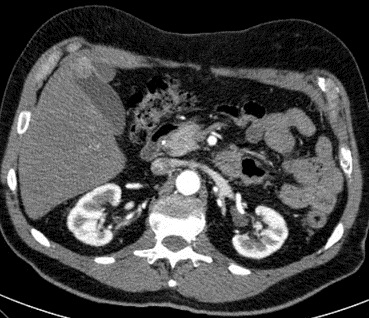

Imge TDM de polyp vesiculaire

est : image de l' aspect bourgeonaise ou polypoide a isodense

situe au fond ou au ventre de la vesicule biliaire . Sur la

technique TDM + de contrast intra veineuse la rehaussement peripherique

du polyp peut se en voyait

Image d'une polyp vesiculaire

a isodene situe au fond de la vesicule biliaire .

Image radiologique TDM + contrast en phase

arterielle et coupe axiale |